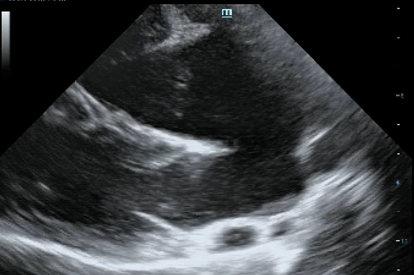

Для диагностики и оценки степени тяжести врожденного порока сердца необходимо проведение таких диагностических процедур как: осмотр, рентгенография, эхокардиография с применением цветовой допплерографии, контрастная эхокардиография, КТ- диагностика с применением контраста. После постановки диагноза и определения степени тяжести можно разобрать варианты лечения и дать прогноз.

Рисунок 5 Эхокардиография с применением контраста